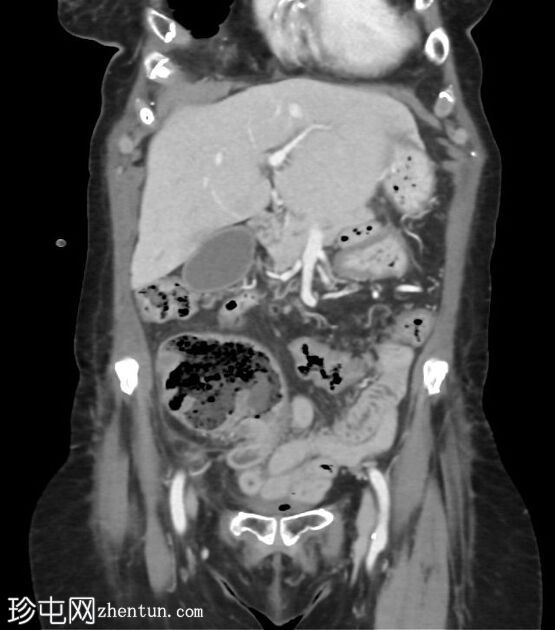

冠状C+门静脉期

阑尾盲肠极-基底部明显增厚,强化明显。阑尾中段1/3直径扩张至12毫米,远端1/3增厚。阑尾尖端周围有微小组织性液体积聚。阑尾周围无明显脂肪条带。

轻度门静脉周围血流痕迹。大量胆结石。L2-L3-L4节段后路椎板切除术后,因L2-L3节段大量钙化性椎间盘突出释放压力。子宫脱垂术后。腰椎侧凸,向左凸。